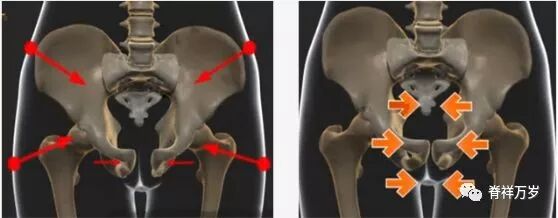

恥骨結合炎の原因:急なストップや方向転換が原因 恥骨結合を動かすカは、左右の骨盤をずらすような動きによって発生します。 急停止や方向転換がこれに相当します。 そのため、このような動きをすることが多いスポーツで、恥骨結合炎が多く発生しています。 サッカー、ラグビー、アメリカンフットボールなどが、恥骨結合炎を起こしやすい典型的な競技07/04/16 · 恥骨がチクチク痛む病気 恥骨骨炎 恥骨骨炎は、次の通り恥骨に起こる炎症のことです。 鼠径部や膀胱、前立腺の手術後に感染症を起こすことで、発症するケースが最も多いです。 〜40歳代の若年女性に多い のが特徴です。 恥骨骨炎では、恥骨結合を23/08/17 · 恥骨炎 恥骨のある部分は骨と骨が接近しており、その接合部分が何らかの影響で炎症を起こしてしまうことです。痛みを発症していますので、速やかな診断が望まれます。 炎症を引き起こしていることなので、薬物での対応で痛みは治まります。

耻骨错位 脊祥万岁 微信公众号文章阅读 Wemp